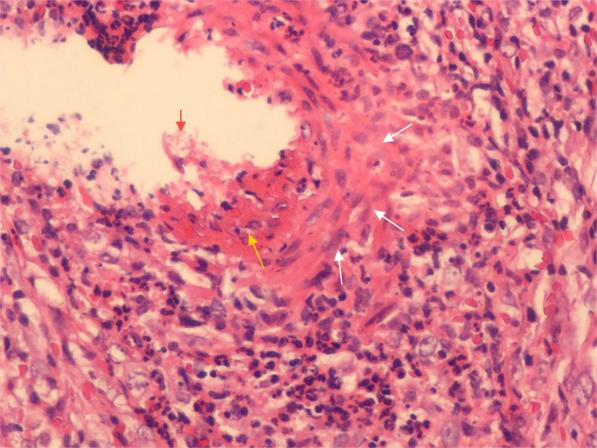

初步检查显示,类风湿因子、抗核抗体谱等指标均正常,排除了典型类风湿关节炎、系统性红斑狼疮等导致。而下肢红斑处皮肤活检更是揭示出重要发现:考虑皮肤血管炎,抗酸染色(-)。

结合患者反复口腔溃疡、下肢红斑、关节症状和病理结果,解开了十年疼痛的谜底:白塞病(Behçet's disease,BD)!在给予激素和免疫抑制剂治疗后,患者病情逐渐缓解。